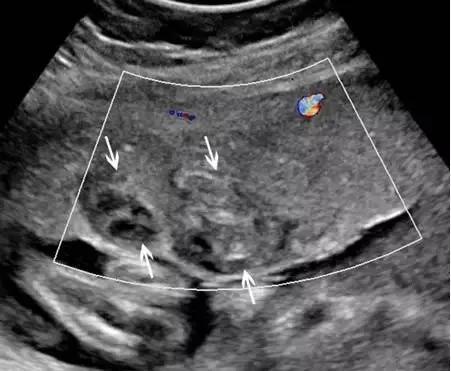

超声最早可在孕 6 周(经阴道超声)或孕 10 周(经腹部超声)显示出胎盘,表现为妊娠囊周围的薄层环状高回声。妊娠 12~13 周时,多普勒超声可显示绒毛血流。孕 14~15 周时,胎盘已充分发育,表现为显著的高回声。此时,也可看到由蜕膜、肌壁、子宫血管等组成的胎盘后复合体(图 1)。

中孕时,胎盘逐渐成熟变大,表现为更加均质的高回声(图 2),其内可有边界欠清的低回声区,为胎盘湖。晚孕时,多普勒超声可显示胎盘内的丰富血流。

图 1 孕 12 周时的正常胎盘矢状面,其后可见低回声的胎盘复合体(小箭头)

图 2 孕 24 周时的正常胎盘横切面,显示胎盘的回声、厚度及其后方的低回声肌壁(箭头)